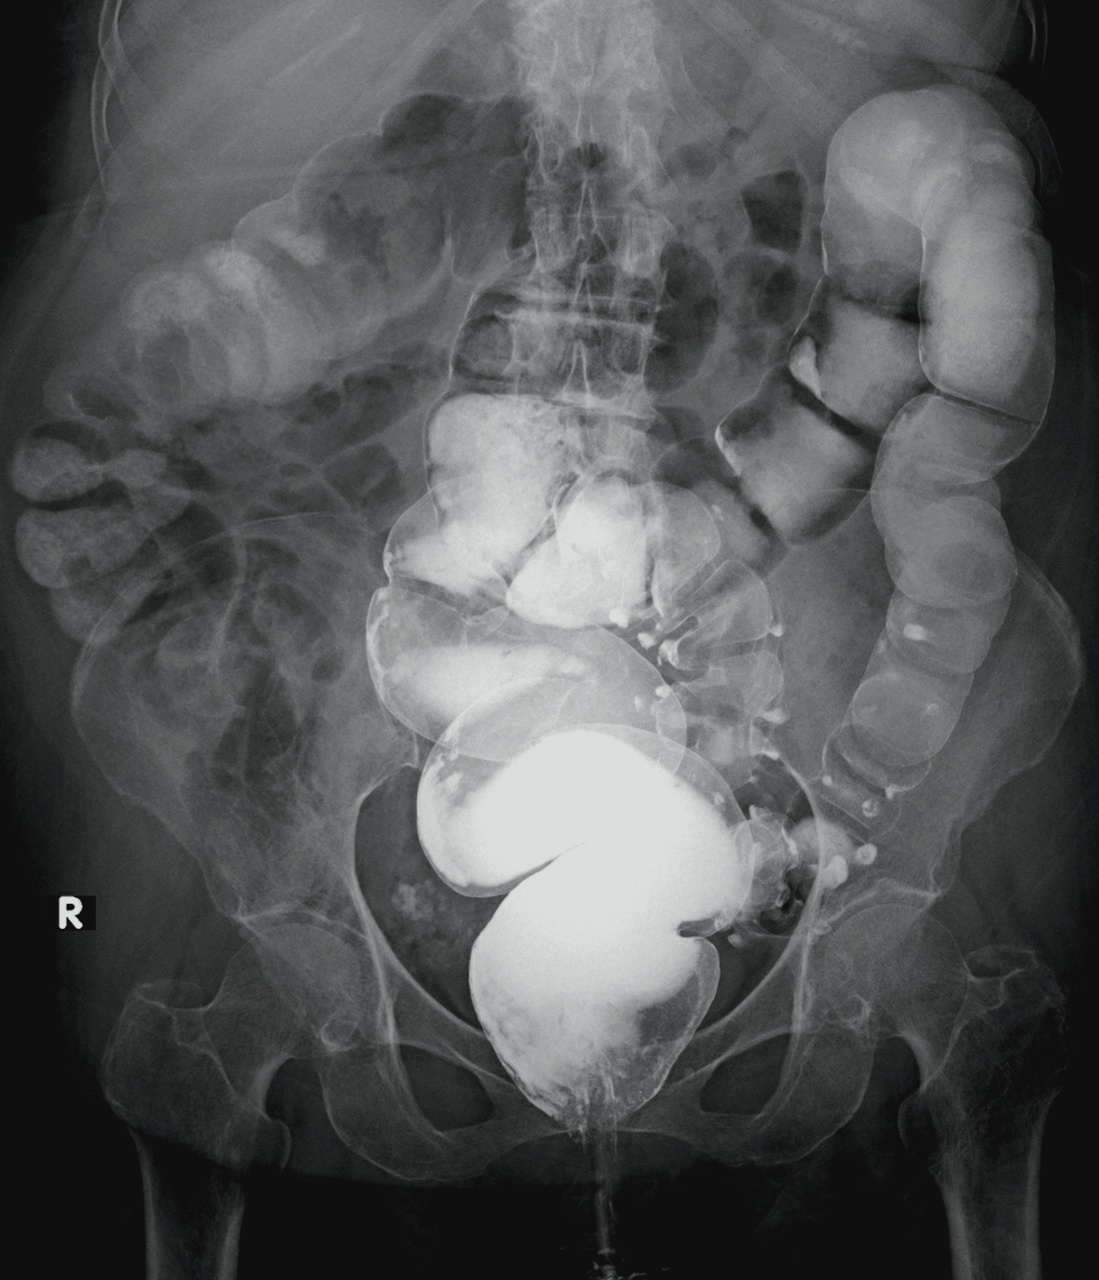

Le scanner abdomino-pelvien avec injection intra-veineuse de produit de contraste en l’absence de contre-indication (fig. 1) est recommandé en première intention pour le diagnostic et la recherche des complications ;1 l’IRM abdominale est une bonne alternative, notamment en cas d’allergie sévère au produit de contraste ou pour les femmes enceintes. L’opacification digestive basse n’est plus indiquée dans la prise en charge initiale. L’imagerie peut être discutée et parfois omise chez des patients aux multiples récidives et en l’absence de critères de gravité (péritonisme clinique, syndrome inflammatoire marqué…).